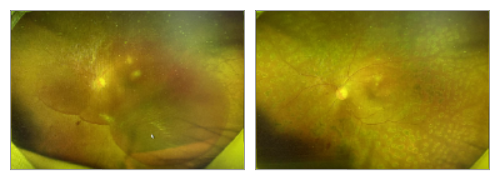

高血压患者的眼底照2

左图眼底照发现上方部分视网膜血管已经完全变白。该患者经过造影检查,显示病灶区大片缺血,给予激光治疗,降低了新生血管发生的风险(右图)。